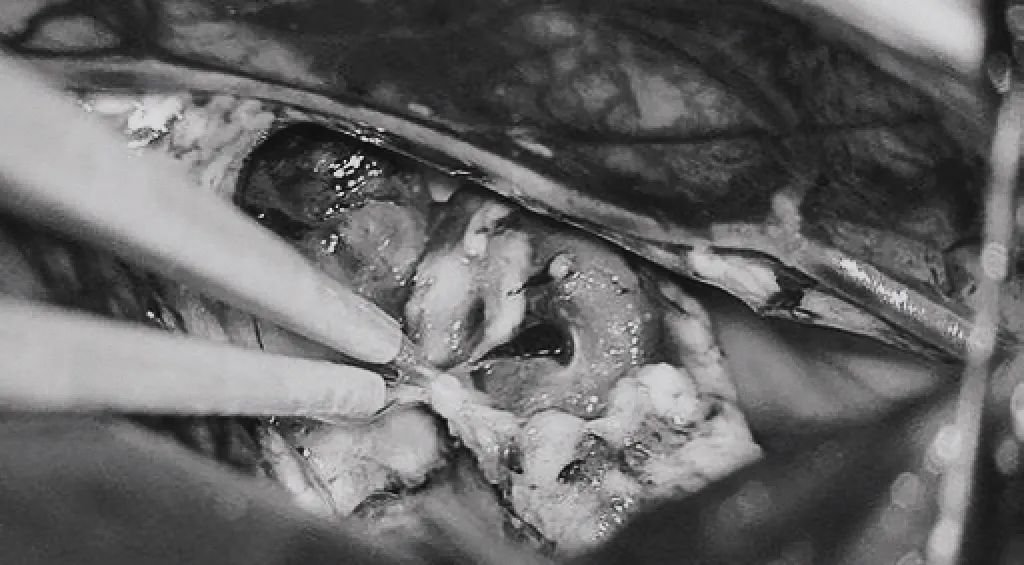

▼(c)双额开颅,打开纵裂(鼻朝右,中线水平位,重力牵拉右侧半球),显露胼胝体、CmaA和PcaA。(d)切开胼胝体2.5cm,显露透明隔内的AVM,大致显露ACA。

▼(e)将AVM后缘向前牵离穹窿。

▼(f)在透明隔底部保留FoM、穹窿和右侧SepV。

▼(g)引流静脉变黑。

▼(h)引流静脉进入ICV处电凝。完全切除AVM。